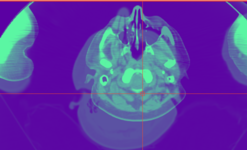

| + | Image:Plastimatch_icon.png|NEW: [[Modules:Plastimatch |Plastimatch non-rigid registration]] (Greg Sharp) | ||

NEW: Plastimatch non-rigid registration (Greg Sharp)

Plastimatch non-rigid registration (Greg Sharp)